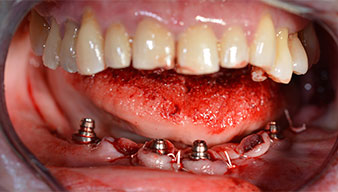

Para la planificación y la minimización del riesgo, se realizó una tomografía volumétrica tridimensional (TVD, Planmeca) que mostró que la calidad y la cantidad del tejido óseo era suficiente para la intervención quirúrgica y el tratamiento inmediato con el método Fast & Fixed. Siguiendo el protocolo de este método, se insertaron los implantes en la región de las piezas 35, 32, 42 y 45. Debido a la inclinación de hasta 45 grados de los implantes distales, el perfil de emergencia se desplazó hacia posterior y se generó un mayor polígono de soporte (fig. 3).

El siguiente ajuste programado es la propia inserción de los implantes. En nuestra clínica, solemos insertar los implantes con una fuerza de 32 Ncm de manera estándar (figs. 12 y 13).

El requisito imprescindible para el tratamiento inmediato es una alta estabilidad primaria. Para satisfacer dicho requisito, en este caso, se prescindió del corte de rosca. La unidad de accionamiento Implantmed de W&H empleada aquí, posee un modo propio para ello que también puede seleccionarse directamente y resulta imprescindible para muchas indicaciones. Los últimos giros para la inserción del implante superaron el valor de 32 Ncm, por lo que se realizaron manualmente. En tales casos, se recomienda utilizar la función autocortante de los implantes y girar el implante varias veces hacia delante y hacia atrás de forma que el implante se aproxime gradualmente hasta su posición definitiva sin ejercer una presión excesiva sobre el hueso (fig. 14).

Para compensar la divergencia de los implantes distales, se atornillaron pilares acodados (35 grados) de forma que los perfiles de emergencia de todos los implantes quedaran en la posición más vertical posible en relación con la mordida. Este paso es necesario para poder atornillar de forma oclusal el tratamiento provisional y, posteriormente, el definitivo (figs. 15 y 16).